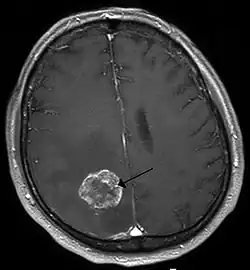

- Brain tumor